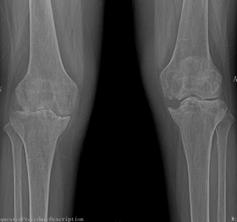

2015年10月,我院骨科二區(qū)迎來了62歲的李姓患者,她是一名類風濕性關(guān)節(jié)炎的患者,病程10年。10年前,她被查出患有嚴重的類風濕性關(guān)節(jié)炎,全身多處小關(guān)節(jié)疼痛,自那以后,患者就長期依靠激素來控制病情。2年前,患者雙側(cè)膝關(guān)節(jié)開始出現(xiàn)疼痛、腫脹,起初還能下地走200米左右,后來走50米都感覺費力,雙下肢膝關(guān)節(jié)出現(xiàn)變形,靠鎮(zhèn)痛藥物才能入睡。起初患者認為,類風濕關(guān)節(jié)炎是自己的老病,沒得治,拒絕來醫(yī)院就診。最后,實在痛苦難忍,遂在家人的陪伴下來到我院骨科二區(qū)就診。

來院后,骨科二區(qū)唐雄主任、廖浩主治醫(yī)師熱情接待了她。經(jīng)查,患者為嚴重的類風濕性關(guān)節(jié)炎導致的雙膝關(guān)節(jié)破壞,雙膝關(guān)節(jié)內(nèi)翻畸形并嚴重的骨質(zhì)缺損,同時由于患者長期服用激素類藥物,其全身骨質(zhì)均有嚴重的骨質(zhì)疏松?;颊叩弥∏閲乐匦院螅械绞?、沮喪,唐雄主任信心滿滿地安慰道,“您這種情況行膝關(guān)節(jié)置換術(shù),就能徹底解決關(guān)節(jié)疼痛和雙膝關(guān)節(jié)不能活動的問題?!庇谑牵∪擞种匦氯计鹆藢ι畹南M?,并要求盡快進行手術(shù)治療。